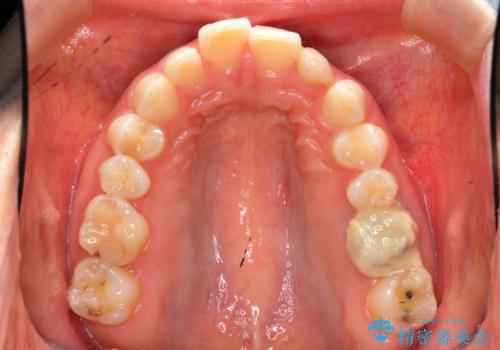

出っ歯を治したい 過蓋咬合

- 出っ歯を主訴に来院。

かみ合わせが深く、治療に時間がかかりました。

上顎2番は矮小歯だったのをセラミックで被せています。

口唇の突出感がなくなり、理想的な横顔になりました。